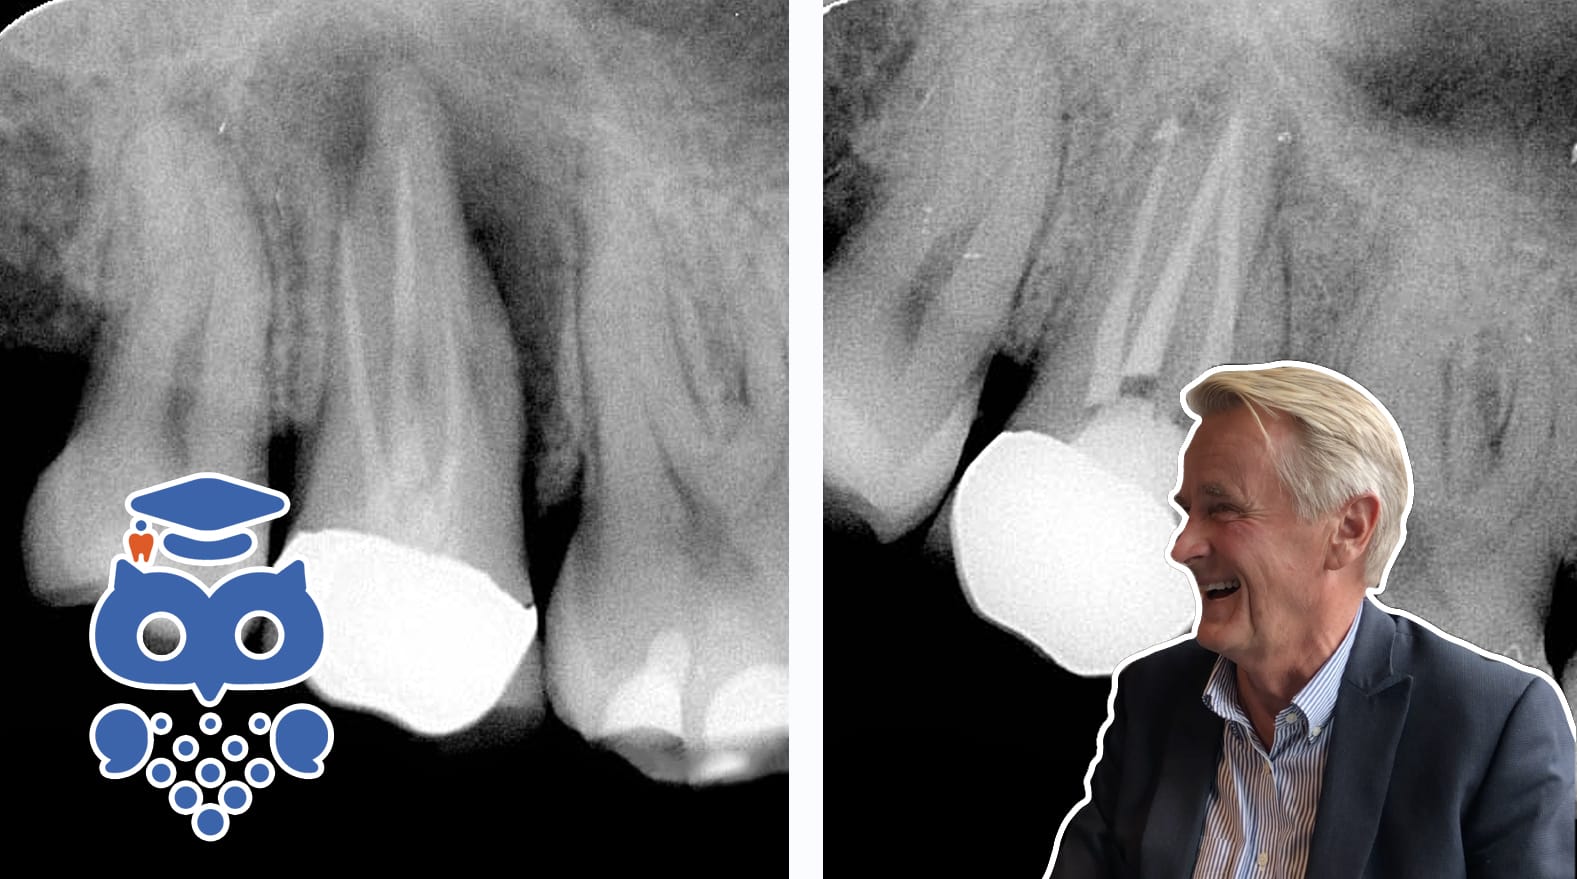

Ortograd revisionsbehandling används för att behandla kvarstående eller tillstötande apikal parodontit, eller för att förbättra rotfyllningens kvalitet. Behandlingen inkluderar rotfyllningsavlägsnande, desinfektion och rotfyllning. Prognosen är god.

Revisionsbehandling kan bli aktuell när den rotfyllda tanden visar kliniska och eller radiologiska tecken på kvarstående eller tillstötande apikal parodontit. En sådan behandling kan utföras med tillträde till roten genom ett kirurgiskt ingrepp (retrograd rotbehandling) eller som ortograd revisionsbehandling. Se faktablad om Retrograd rotbehandling

En ofullständigt rotfylld tand har sannolikt en förhöjd risk att infekteras om rotkanalerna kommer i kontakt med munhålans bakterier. Revision av rotfyllningen på så kallad teknisk indikation (i avsaknad av apikal parodontit) kan således vara motiverad för att förbättra rotfyllningens kvalitet och förebygga apikal parodontit i samband med, till exempel, en stiftförankring av en tidigare rotfylld tand.